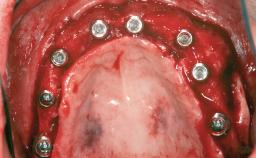

Shell Technique for Horizontal and Vertical Maxillary Bone Augmentation in a Partially Edentulous Patient with Aggressive Periodontal Disease

A 46-year-old woman was referred for treatment whose main complaints were mobility of her fixed partial dentures (right maxilla and left mandible) and periodontal bleeding during function. She also reported having taken systemic antibiotics to treat recurrent swelling in the area of the upper left molars. The patient had not seen a dentist for at least 2 years. She did not smoke and had no history of major systemic disease other than two minor orthopedic procedures some years back. The first-visit examination revealed poor plaque control, tooth mobility, periodontal disease, and a residual dentition widely associated with deep periodontal pockets.

Bone Augmentation Horizontal|Staged|Vertical

Augmentation Materials Autogenous chips|Autogenous block(s)|Xenogenous